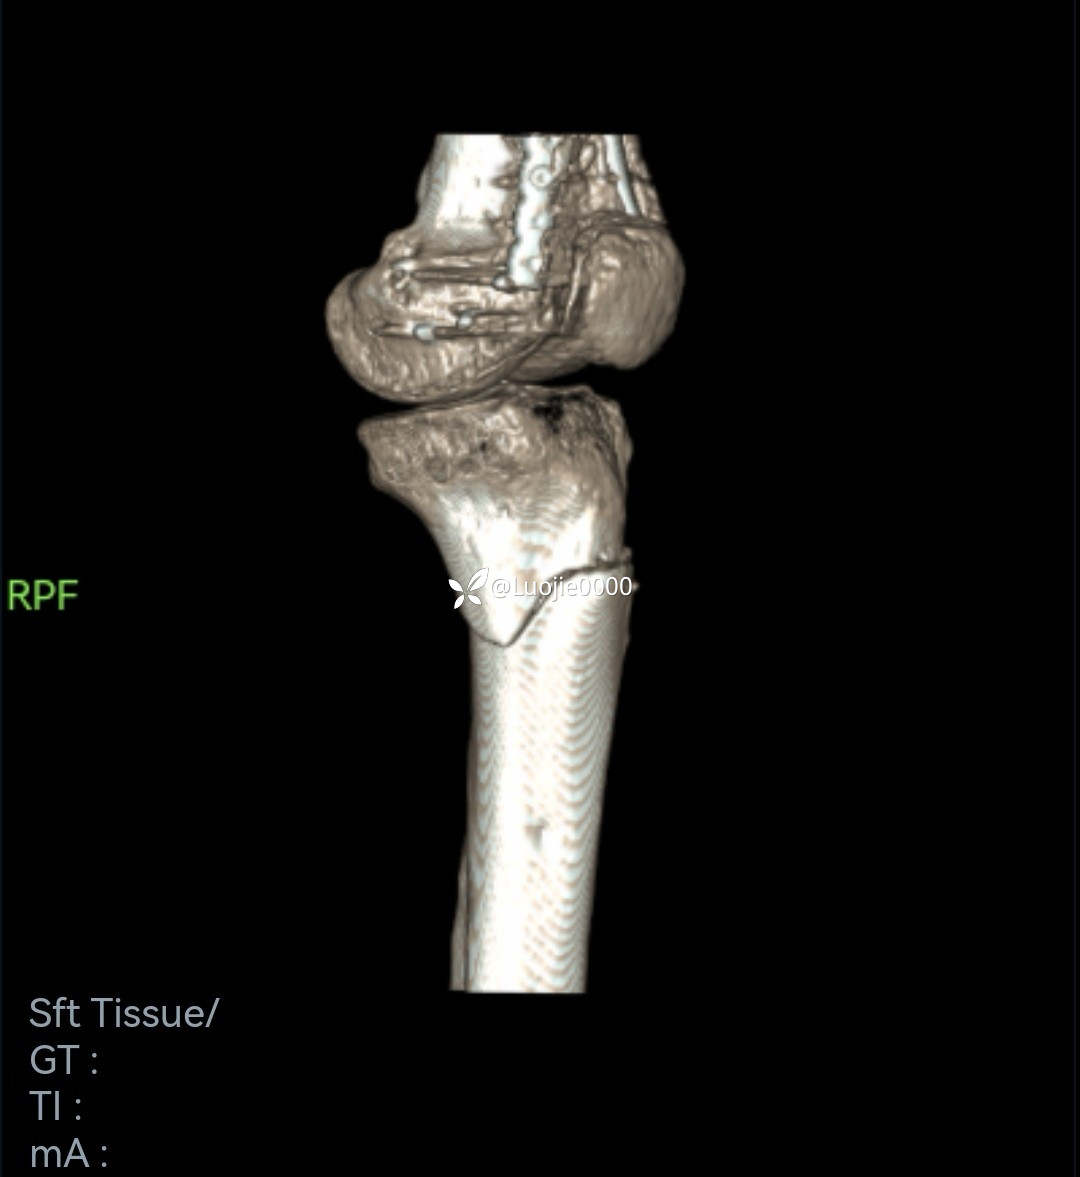

辅助检查:DR及CT提示:左胫骨近端及腓骨头骨折。

影像资料如下:

照书做没成功

切开复的位